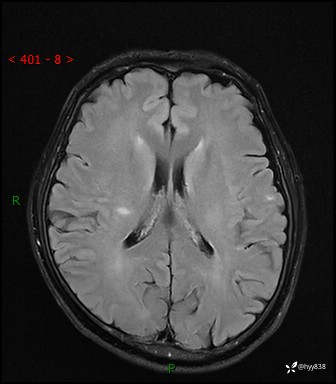

颅脑MRI平扫